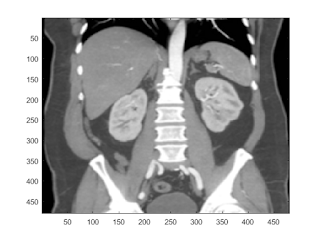

gaussian filter

note: pick filter size appropriately imagausfilt avoids this problem

I=single(I); b = fspecial('gaussian',32,2); I2 = conv2(I,b,'same'); imagesc(I2);